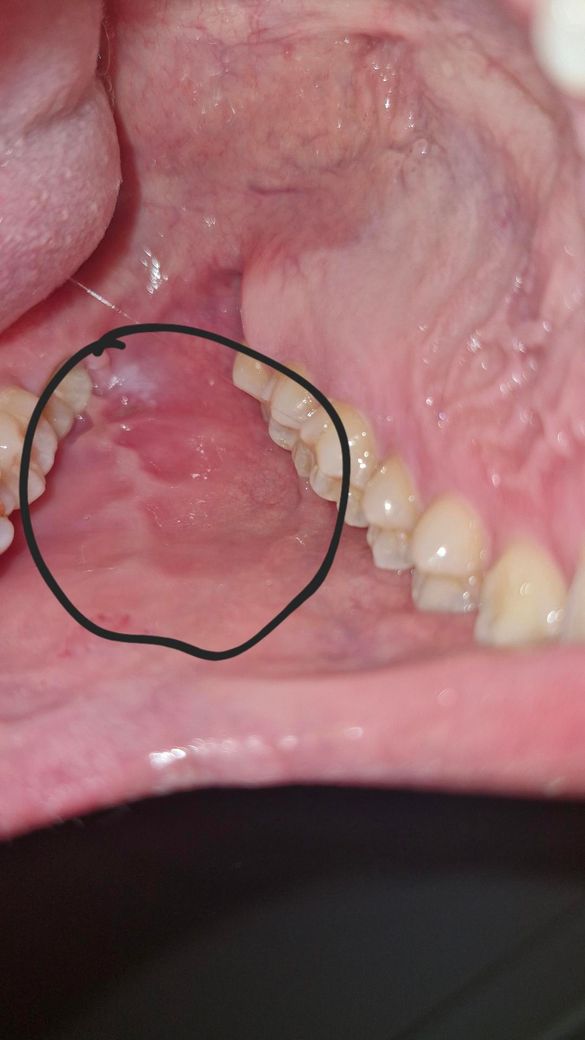

사랑니 근처 볼 내부가 조금 부었습니다

생긴진 2일 정도 된거같고 처음엔 붓지도 않고 그냥 따갑고 혀로 만졌을때 뭔가 동그라미에 중간에 패인 느낌이 있어서 아 구내염이구나 하고 넘겼는데 2일차 되니 부은게(내부에서) 확실히 보일 정도라 걱정되네요..

• 1번 째 사진

사랑니 부위의 잇몸이 눌린 이유는 반대 쪽에 있는 사랑니가 잇몸을 누르기 때문입니다.

사랑니로 인해 지속적으로 잇몸에 염증이 유발되는 것 같습니다 치과가셔서 사랑니 발치에 대한 상담을 받아보세요